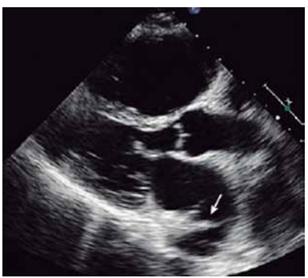

Homem, 60 anos, transplantado cardíaco, vem realizar ecocardiograma que identifica a seguinte imagem:

(Arquivo pessoal; imagem utilizada com autorização)

A imagem apontada pela seta indica:

A

sutura.

B

trombo.

C

veia pulmonar.

D

septo atrial.

E

artefato.